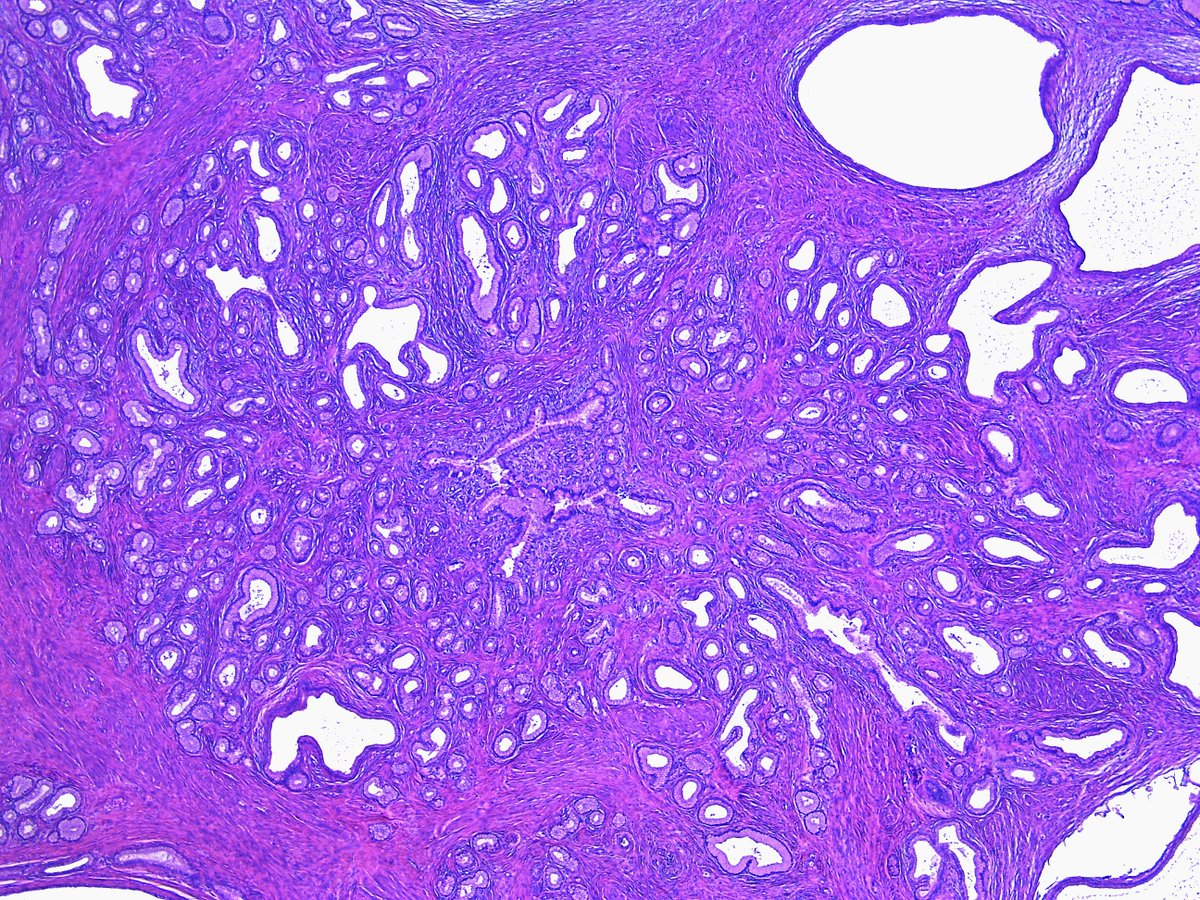

A, Brunner gland hyperplastic nodule/polyp. At low power, hyperplastic Glandular Hyperplasia Meaning It's also called an enlarged prostate. Cystic endometrial hyperplasia is a type of endometrial hyperplasia without atypia, which means the lining of the uterus grows too thick due to estrogen imbalance. Hyperplasia is an increase in the number of cells in an area of the body, causing tissue enlargement. It can be benign or. Benign prostatic hyperplasia (bph) is a. Glandular Hyperplasia Meaning.